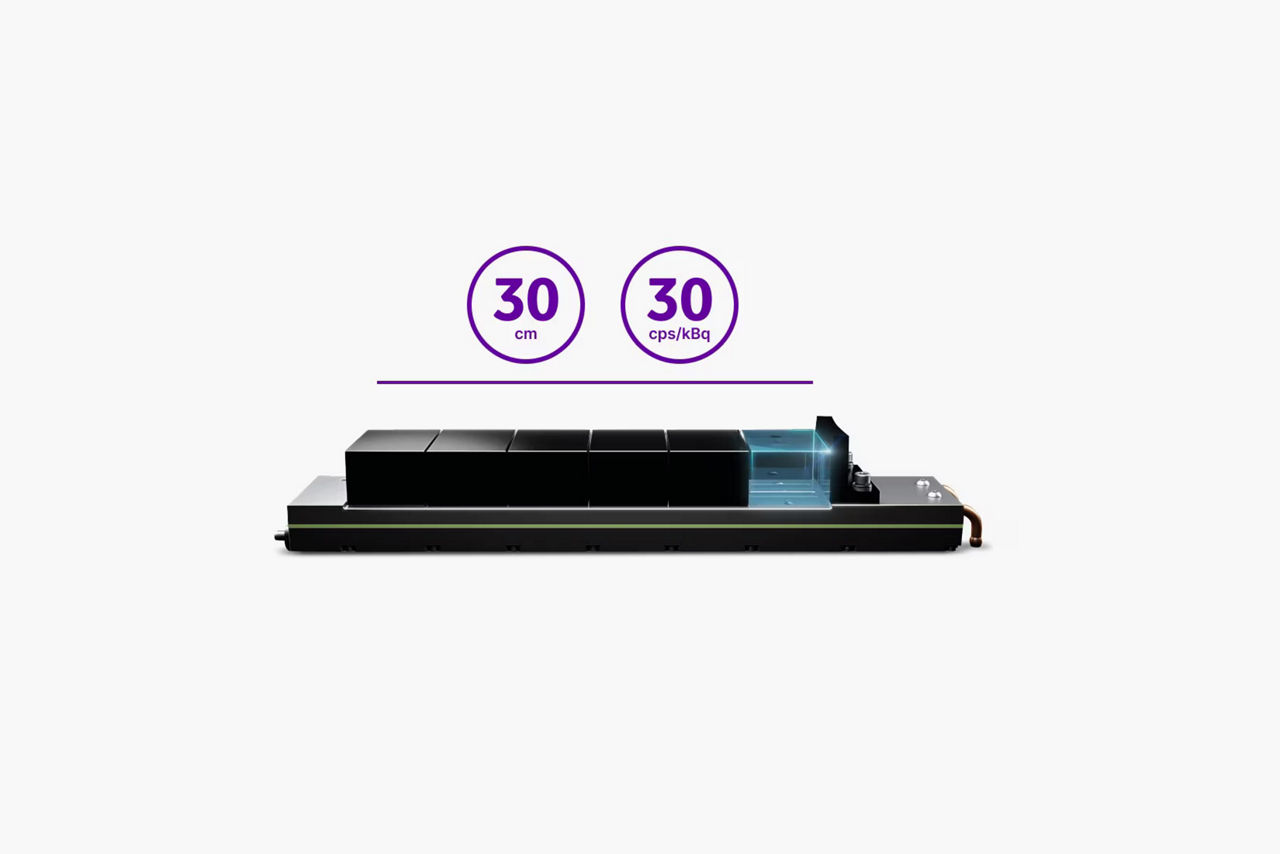

Up to a 41% increase in small lesion detectability1

High sensitivity

Achieve a 125% increase in sensitivity2

Up to a 41% increase in small lesion detectability1

High sensitivity

Achieve a 125% increase in sensitivity2